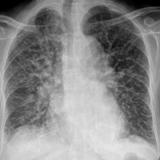

APE 2

Date: 11/05/2005

Views: 2808